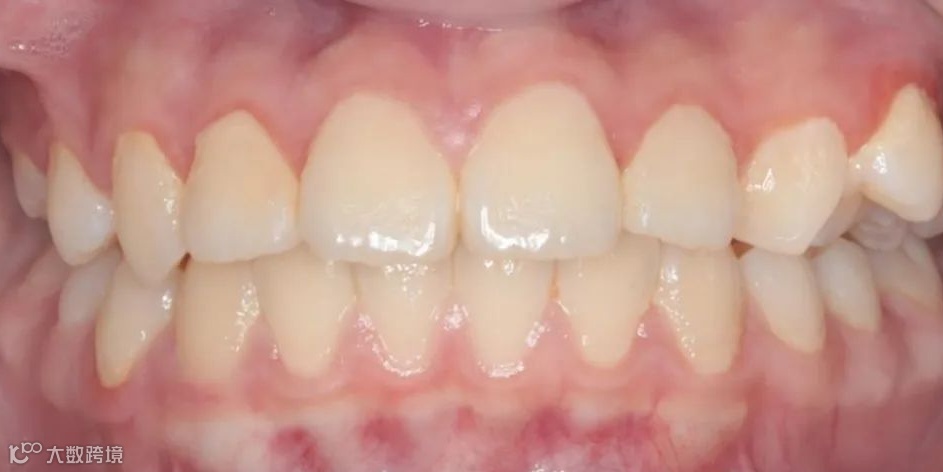

治疗前正面咬𬌗相

治疗后正面咬𬌗相

治疗前正面微笑相

治疗后正面微笑相